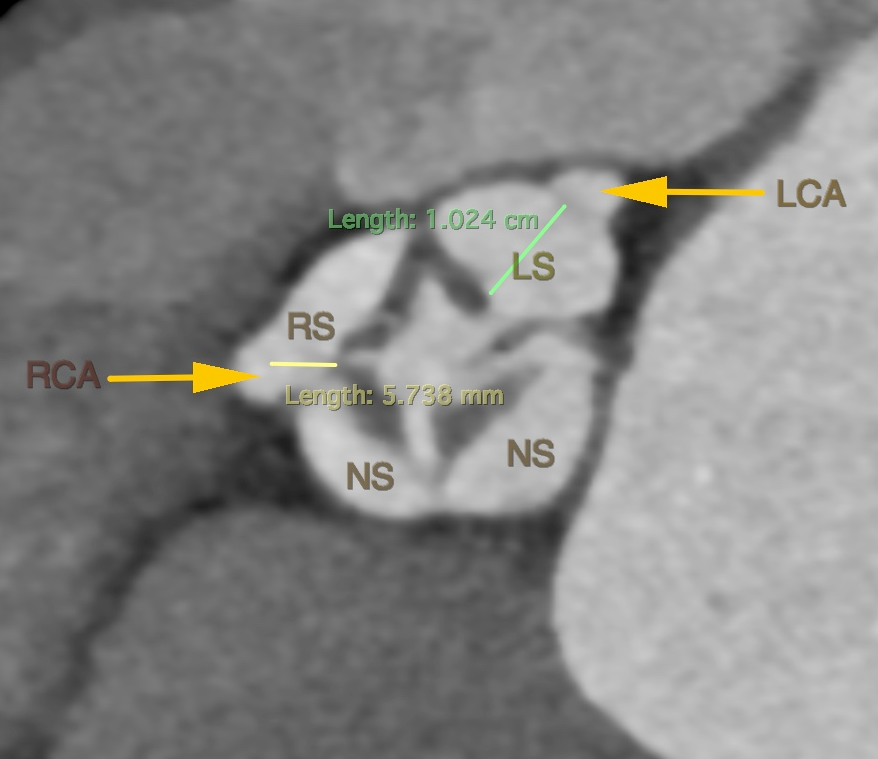

左冠风险评估

图片

右冠风险评估

• 术前CT预估21mm人工瓣膜植入后位置及STJ层面残余空间。患者右-无、双无冠状窦少量粘连,预计瓣膜植入后向左右冠窦方向偏移。

• 考虑到术后可能需要植入冠脉保护支架,因此选择大网孔的VitaFlow®瓣膜,为术中/术后冠脉介入提供保障。